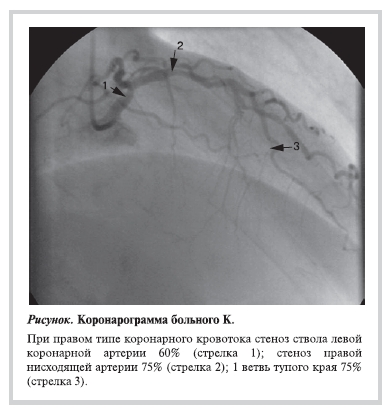

больному проведена коронарография (КГ), на которой выявлены (см. рисунок) стеноз ствола левой КА 60%, серия стенозов передней нисходящей артерии (ПНА) до 75% и 1-й ветви тупого края (ВТК) до 80%.

Что следует делать при выявлении такого поражения КА согласно рекомендациям ЕОК? Они гласят следующее: «Профилактическая реваскуляризация миокарда перед операциями высокого риска может быть проведена у больных с доказанной ИБС (класс IIb B)». Отмечаем первое противоречие предложенной концепции: у больного возможно проведение реваскуляризации миокарда при наличии доказанной ИБС, но по предложенному алгоритму предоперационной оценки выявление ИБС перед хирургическим вмешательством не является обосно ванным! Следующее противоречие — класс